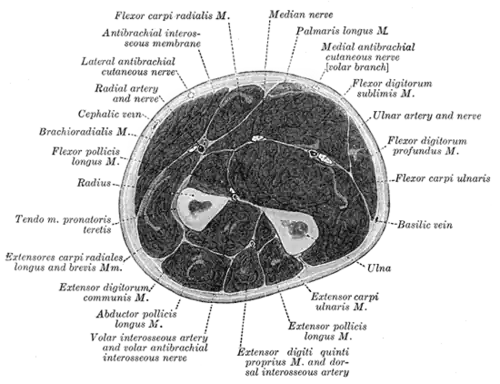

Der Unterarm des Menschen (und den meisten anderen Tetrapoda) besteht aus zwei langen Knochen, der Elle (Ulna) und der Speiche (Radius). Zwischen beiden Knochen liegt ein Spalt (Spatium interosseum antebrachii). Beide sind über ein Band (Ligamentum anulare radii) und eine feste bindegewebige Platte (Membrana interossea antebrachii) miteinander verbunden.

Die Muskeln des Unterarmes werden ihrer Lage nach in zwei Gruppen unterteilt: Die Muskeln, die am lose hängenden Arm innen liegen und somit den Arm anbeugen (Flexoren) und die Muskeln, die außen liegen und den Arm strecken (Extensoren). Diese beiden Gruppen bestehen jeweils aus zwei einzelnen Schichten, die von der Körperoberfläche in die Tiefe gehen.

Die Unterarmfaszie (Fascia antebrachii) grenzt die einzelnen Muskelbäuche voneinander ab. Außerdem teilt sie zusammen mit der Bandhaft zwischen den beiden Unterarmknochen (Membrana interossea antebrachii) die Unterarmmuskeln in eine Beuger- und eine Streckerloge. Im Bereich des Handgelenkes ist sie auf der Handrückenseite durch querverlaufende Faserzüge (Retinaculum extensorum) verstärkt. Diese Verstärkung dient als Haltevorrichtung der Streckersehnen. Auf der Handflächenseite verschmilzt die Unterarmfaszie mit den vorderen Faserzügen (Retinaculum flexorum), welche den Karpaltunnel bilden, durch den die Sehnen der Fingerbeugemuskeln verlaufen. Von dem Musculus biceps brachii geht eine zusätzliche Verstärkung der Faszie aus (Lacertus fibrosus).

Der Unterarm erhält sein Blut zum größten Teil durch die vom Oberarm kommende Oberarmarterie (Arteria brachialis). Diese gabelt sich in der Ellenbeuge in zwei Gefäßäste, die an seiner Speichenseite (Arteria radialis) bzw. Ellenseite (Arteria ulnaris) zur Hand laufen.

Vom hinteren Venennetzwerk der Hand geht auf der Speichenseite die äußere Vene (Vena cephalica) und auf der Ellenseite die innere Vene (Vena basilica) ab. Weiterhin verläuft die mittlere Unterarmvene (Vena intermedia antebrachii) auf der oberen Vorderseite des Armes. In der Ellenbeuge besteht eine Verbindung zwischen der äußeren und der inneren Vene, die gemeinsam als mittlere Ellenbeugenvene bezeichnet wird (Vena mediana cubiti). Diese wird häufig zur intravenösen Injektion oder zur Blutentnahme verwendet.

Die Innervation der Unterarmmuskulatur erfolgt vor allem über die aus dem Plexus brachialis stammenden Fasern des Nervus radialis, Nervus medianus und Nervus ulnaris.

Der Nervus radialis innerviert die Muskeln des Unterarmrückens, die Strecker und außerdem die Haut von Teilen des Daumens und des Handrückens. Der Nervus medianus innerviert die meisten Muskeln der Beuger und außerdem die Haut auf der Innenseite der Hand zwischen Daumen und Ringfinger. Der Nervus ulnaris innerviert nur den Musculus flexor carpi ulnaris und Teile des Musculus flexor digitorum profundus und außerdem die Haut auf Handfläche und -rücken zwischen Ringfinger und Handkante.